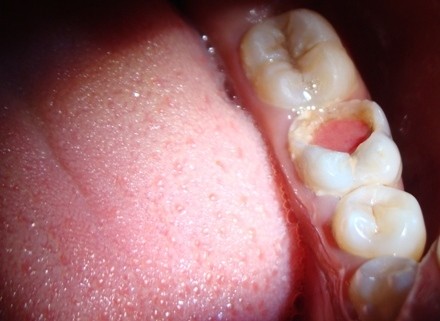

Reversible and irreversible pulpitis

Inside the innermost part of each tooth is an area called the pulp. And Pulpitis is inflammation of the dental pulp, or tissue in the center of a tooth. The dental pulp comprises soft connective tissue, nerves, and the blood supply for the tooth.

There are two forms of pulpitis: reversible and irreversible.

Reversible pulpitis refers to instances where the inflammation is mild and the tooth pulp remains healthy enough to save. Irreversible pulpitis occurs when inflammation and other symptoms, such as pain, are severe, and the pulp cannot be saved.

The most common cause of pulpitis is when bacteria irritate the dental pulp through an area of tooth decay, including dental caries.